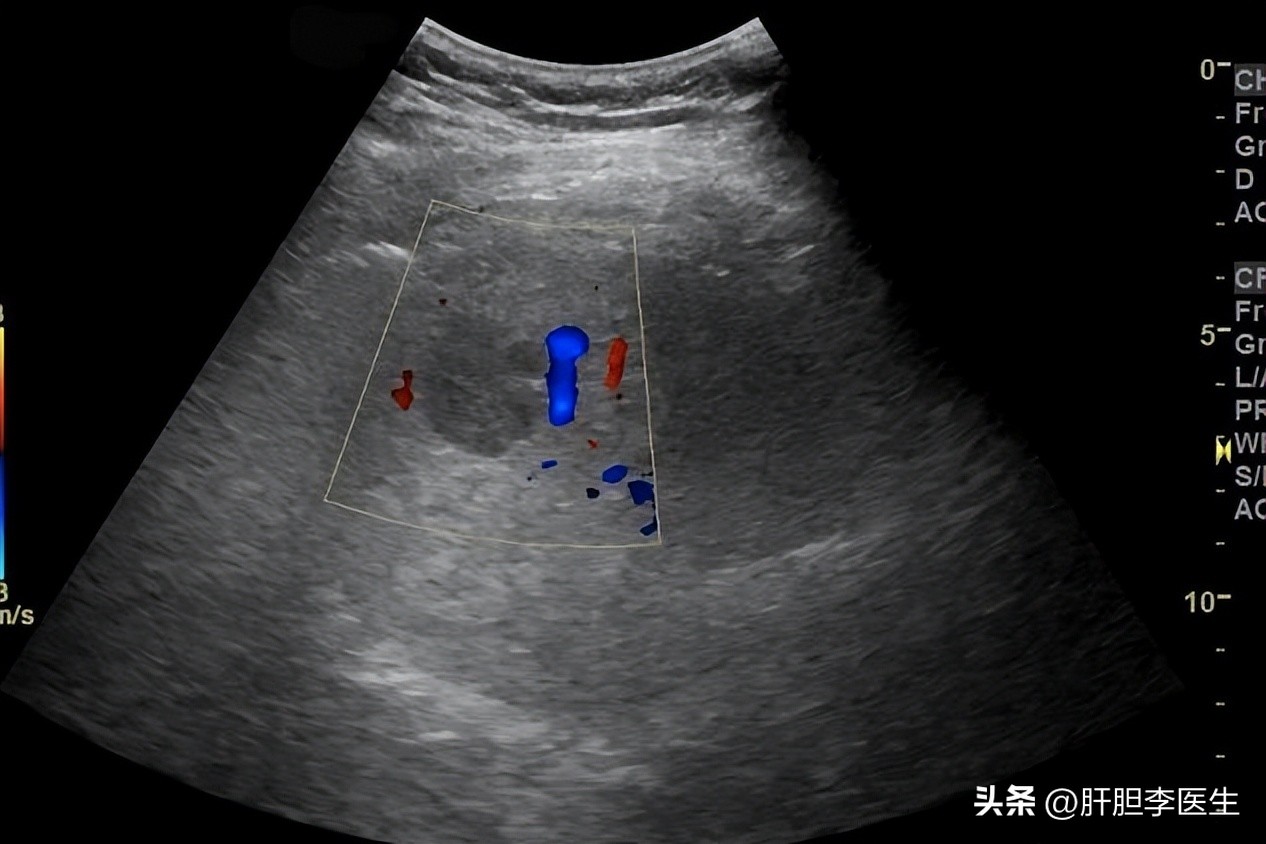

彩超发现肝脏低回声结节

我仔细读着她的彩超报告:右肝可见一低回声结节,大小约2*1cm,边界清晰,回声均匀,未见明显血流信号。结论:肝右叶低回声结节,性质待定。

确实,彩超提示肝脏低回声结节的话,是有肝癌的可能的。肝癌在彩超上的特点,多数都是低回声,所以这位女孩的担心不无道理,再加上网上的关于肝癌的信息,恶性程度之高,且不乏年轻人得肝癌的,自然就会忧心过度。